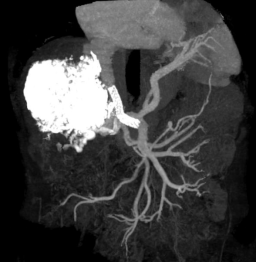

手术历时1+小时,过程顺利,术后肠系膜上静脉造影见支架分流通畅,门体静脉压力梯度由术前20mmHg降至术后8mmHg,手术达到预期目标。术后患者情况稳定,复查CT显示支架通畅,侧支循环消失,5天后好转出院。患者后续需要长期服药治疗包虫病灶。

(左图:术前CT重建 右图:术后CT重建)